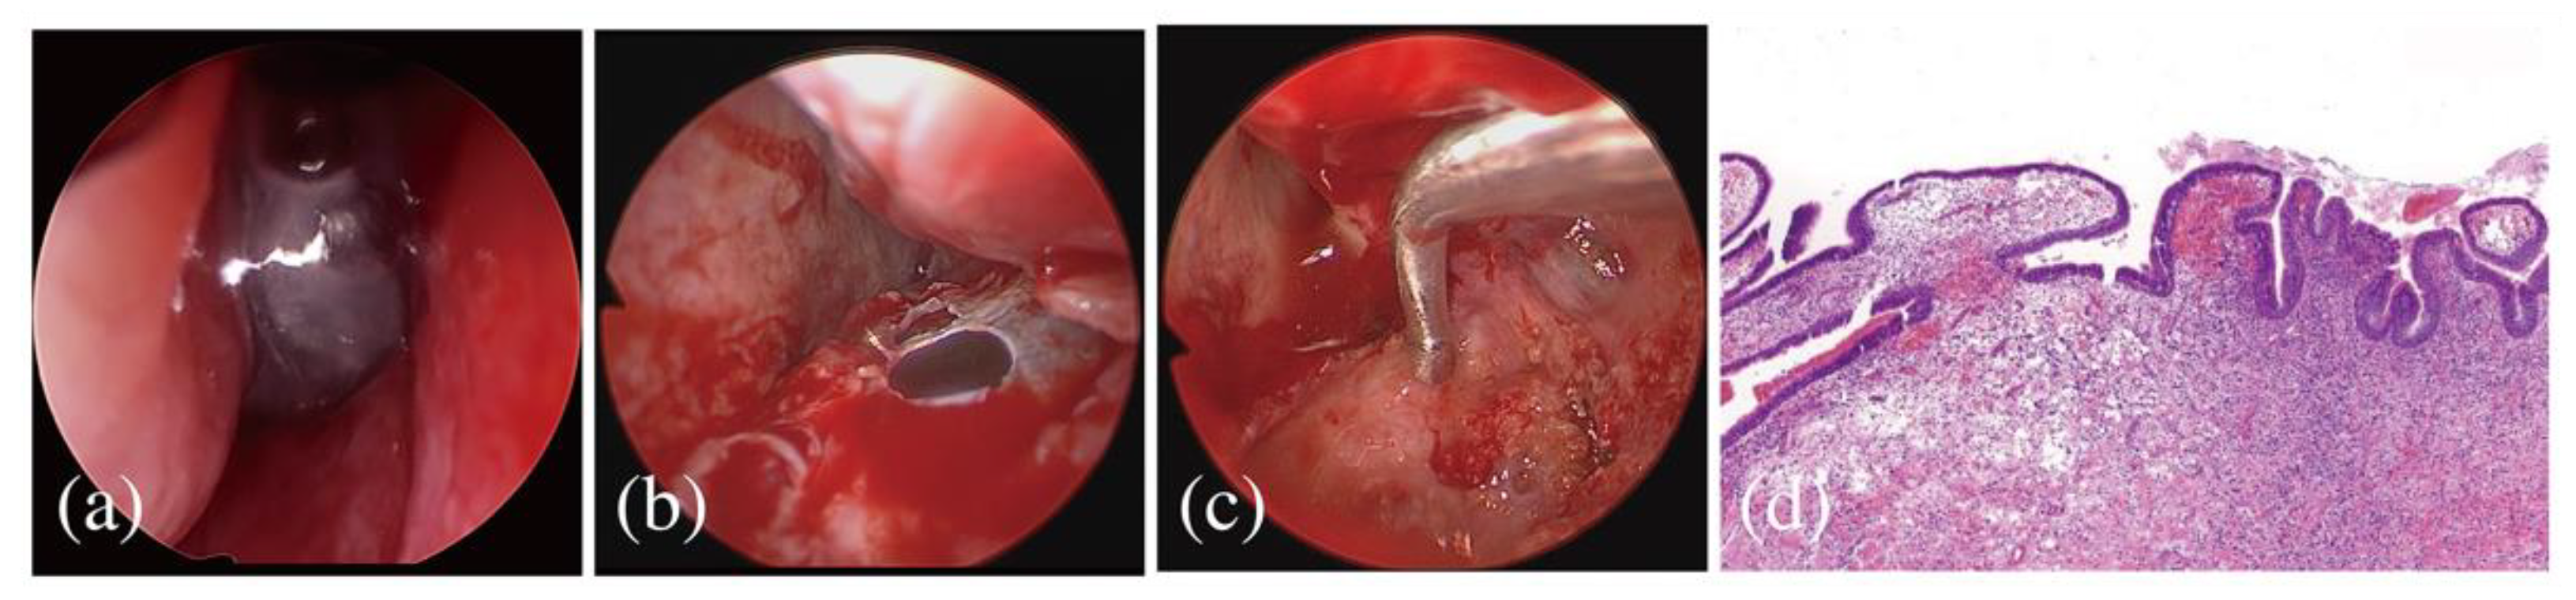

2.3. Referral to an Otolaryngological Specialist

2.4. Follow-Up